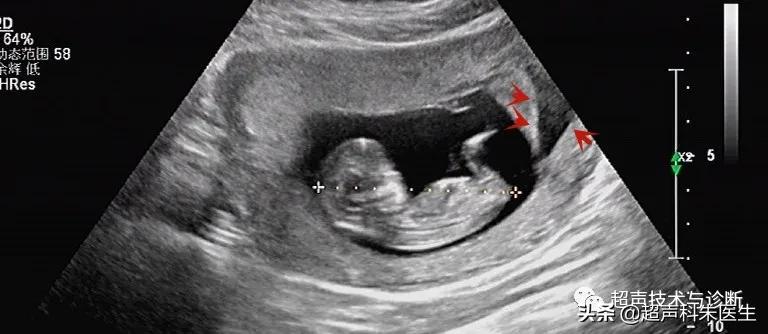

出现绒毛膜下血肿的孕妇,仅有20%会出现阴道不规则流血或下腹部疼痛的症状,而其余大多数绒毛膜下血肿是在超声检查中发现的,其超声表现为:子宫壁和胎膜(或孕囊)之间的无回声区,多位于胎盘下缘至宫颈内口间,以弧形或新月形多见,若血肿较多或血肿形成时间较长时,内可见点、絮状弱回声及条带状强回声,彩色多普勒超声检查:血肿内无血流信号。

接下来我们来看看具体病例: